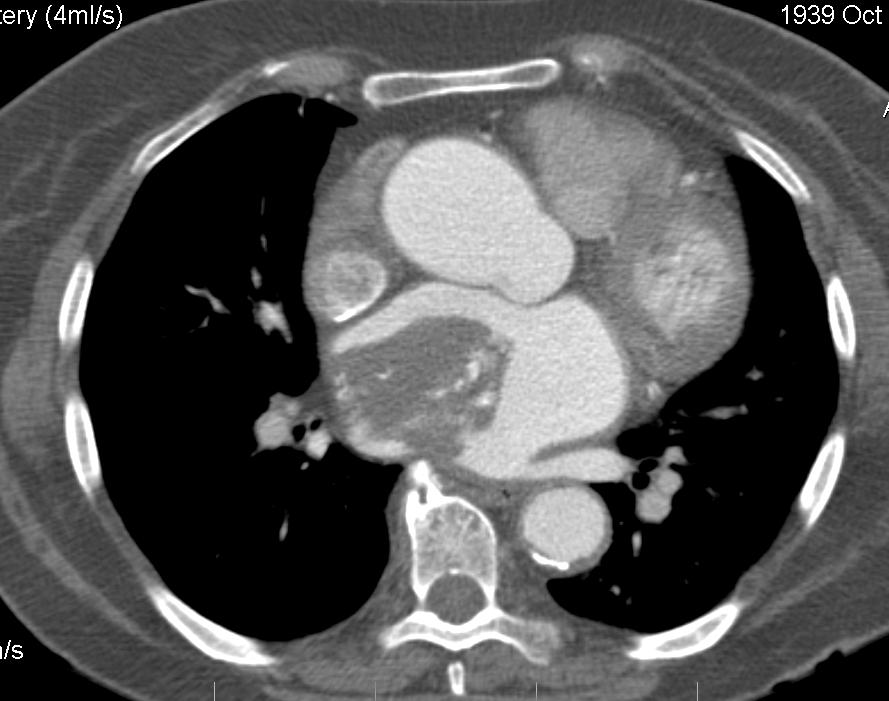

- МРТ – метод, который позволяет изучить особенности кровотока и пролиферативную активность. Исследование проводится с использованием специального контрастного вещества – гадолиния.

Наиболее информативными методами являются эхокардиография и МРТ, которые позволяют установить наличие опухоли, ее характеристики, размеры и степень подвижности. Остальные методы диагностики могут быть менее надежными, но их применение важно для общей оценки состояния здоровья пациента.

Диагностика миксом

Диагностика миксом сердца включает в себя использование различных методов визуализации, таких как эхокардиография, магнитно-резонансная томография (МРТ) и компьютерная томография (КТ). Эхокардиография является основным методом, позволяющим визуализировать опухоль и оценить ее размеры и локализацию. В некоторых случаях может потребоваться биопсия для подтверждения диагноза.